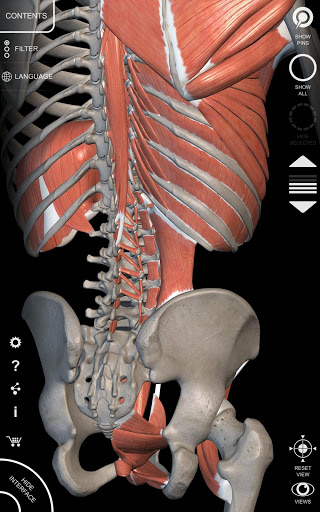

يتيح لك "Anatomy 3D Atlas" دراسة التشريح البشري بطريقة سهلة وتفاعلية.

من خلال واجهة بسيطة وبديهية، من الممكن ملاحظة كل بنية تشريحية من أي زاوية.

تتميز النماذج التشريحية ثلاثية الأبعاد بتفاصيل خاصة ودقة تصل إلى 4K.

يسهل التقسيم حسب المناطق والمناظر المحددة مسبقًا مراقبة ودراسة الأجزاء الفردية أو مجموعات الأنظمة والعلاقات بين الأعضاء المختلفة.

نماذج تشريحية ثلاثية الأبعاد

• الجهاز العضلي الهيكلي

• تصور العضلات من خلال مستويات الطبقات من الطبقات السطحية إلى الأعمق